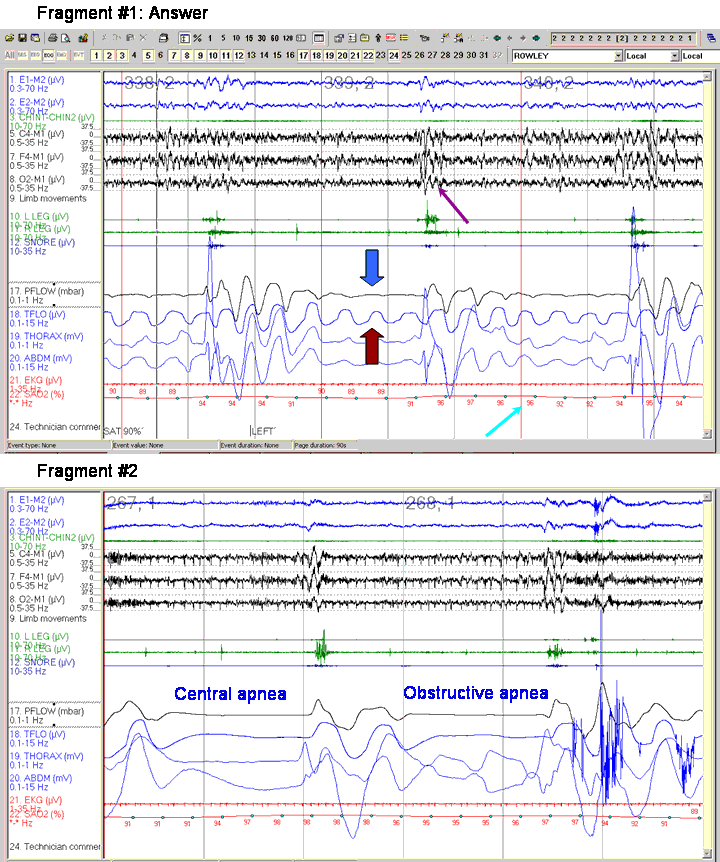

Therefore, an apnea can be scored only if there is the absence of airflow on the oronasal thermal sensor. If there is absence of flow on the nasal pressure transducer but reduced flow on the thermal sensor, the event is identified as a hypopnea. This rule is illustrated in the fragment. For the indicated event, there is no flow in the nasal pressure transducer signal (PFLOW, blue block arrow) but there is continued, though decreased, airflow in the thermal sensor (TFLOW, maroon block arrow). Therefore, this event is a hypopnea. Note also that the hypopnea is followed by both an arousal (purple arrow) and desaturation (aqua arrow).

The new scoring manual provides two definitions of hypopnea. The recommended definition is a drop in airflow ≥ 30% from baseline lasting for at least 10 seconds and associated with a ≥4% desaturation. The hypopnea in this fragment meets this definition (note that the desaturation is from 96% to 92%).

To illustrate an apnea, Fragment #2 is also presented. This is a 60-second fragment and shows a central apnea (left epoch) and an obstructive apnea (right epoch). Note that for both apneas, both the TFLOW and PFLOW signals are flat.

Finally, note should be taken that both fragments show the new recommended EEG and EOG derivations. Both eye leads are referenced to M2 (right mastoid). There are now 3 EEG derivations, all referenced to M1 (left mastoid): the classic central and occipital leads (C4-M1 and O2-M1) and the newly recommended frontal lead (F4-M1).